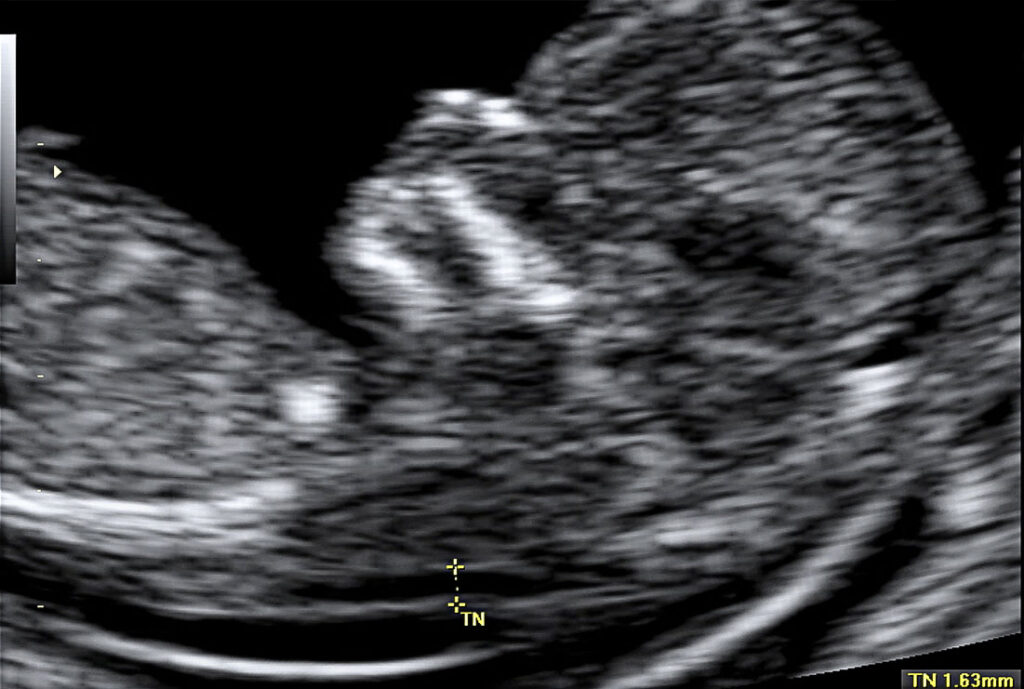

Actualmente entre la semana 11-13s y formando parte del test combinado (cribado de cromosomopatías, por ejemplo síndrome de Down) se debe realizar a todas las gestantes una evaluación ecográfica fetal exhaustiva con la finalidad de hacer una primera valoración morfológica fetal y evaluar varios marcadores ecográficos de cromosomopatías (Translucencia nucal).

En nuestro servicio esta exploración se realiza de forma centralizada, con ecógrafos de gama alta y con personal especializado en este tipo de ecografía con la finalidad de obtener la mejor evaluación posible. Se sigue una evaluación ecográfica de las 11-13 recomendada por la international society of ultrasound in obstetrics and gynecology (ISUOG).